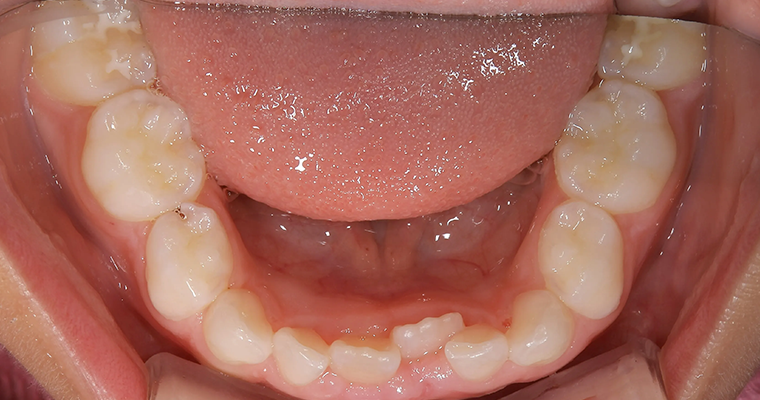

下顎咬合面観

BEFORE

AFTER

| 主訴 | 幼少期から反対咬合 |

|---|---|

| 治療期間 | 10ヶ月 |

| 治療費 | 440,000円(税込) ※調整、器具、治療後にお渡しするEFLine(矯正後の後戻りを防ぐ器具)も全て込みでの金額となっております。 |

| 治療内容 | 6歳で上下拡大 上顎牽引装置 EF Lineで筋機能療法 |